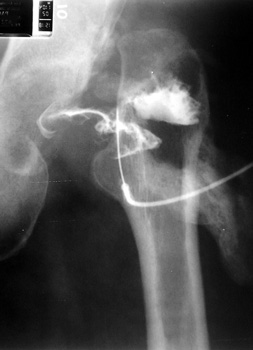

Aspiration of hip after removal of prosthesis. Needle placed

at femoral edge where fluid collects. Needle should not be placed in acetabular

area, which may not be fully intact, risking needle entry into pelvic cavity.